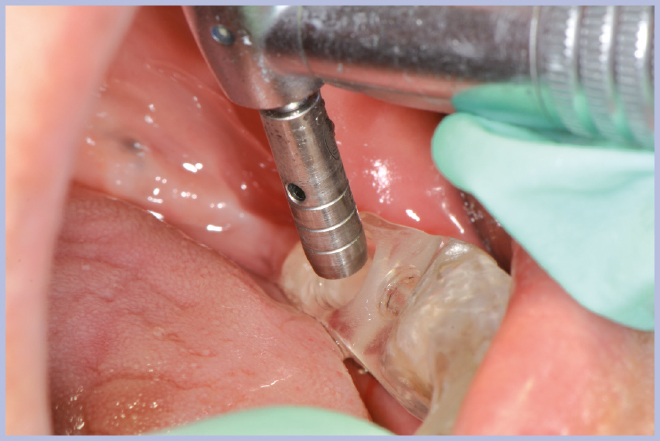

Viene quindi richiesto al tecnico di modificare in laboratorio la mascherina radiologica mediante il posizionamento delle boccole di guida adatte agli impianti da posizionare (Exacone® 6.5 e Exacone® 3,3×8) in asse con gli analoghi del modello Master 3D ed eliminando il repere radiologico standardizzato, trasformandola così nella dima chirurgica (Figg. 14, 15). Si procede quindi alla prova della mascherina sulla paziente per verificarne la stabilità e la corrispondenza esatta con il modello Master 3D (Fig. 16). La seduta chirurgica con tecnica flapless, guida chirurgica e Frese Zero1 dedicate non presenta alcuna difficoltà ; al termine dell’inserimento si posizionano sugli impianti tappi di guarigione bassi per permettere loro di guarire con tecnica sommersa (Figg. 17-27). Si effettua nella stessa seduta una CBCT che dimostra che la posizione clinica degli impianti risulta sovrapponibile a quella progettata dagli Autori (Figg. 28-30).

- Figg. 19, 20 – Passaggio fresa Zero1 attraverso la boccola per impianto Exacone® Ø 3,3

- Fig. 20

- Fig. 21 – Cambio carrier impianto per posizionamento guidato

- Fig. 22 – Posizionamento impianto Exacone® Ø 3,3 con tappo basso